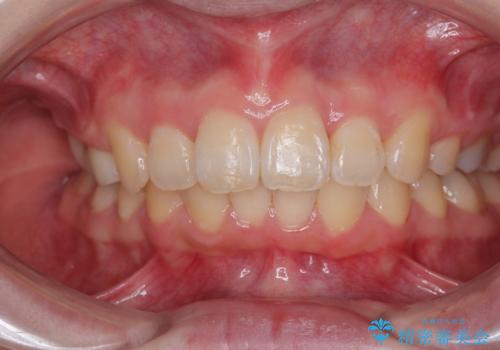

予想通りに治療は困難を極め、その上途中来院されない時期があったため、非常に長期間に及びましたが、周囲の方々が驚愕するほど口元の印象を改善することができました。